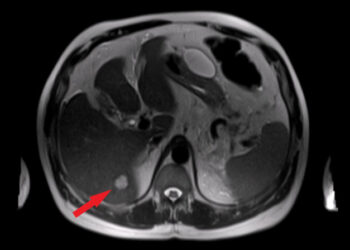

Kepenų siurbikė (fascioliazė): priežastys, simptomai ir gydymas

Kepenų siurbikės – tai parazitiniai kirmėliai, kurie apsigyvena žmogaus kepenyse, tulžies pūslėje arba tulžies latakuose, pažeisdami šiuos organus. Šie parazitai...